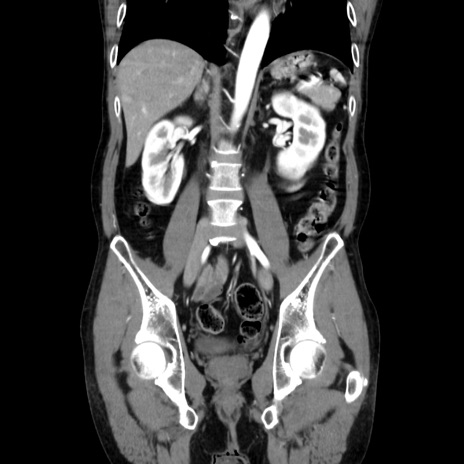

症例37(冠状断像)

【症例】40歳代 男性

【主訴】腹痛

【現病歴】4時間ほど前に電車に乗車中に臍部上より腹痛出現。徐々に増悪し起立困難となり、救急外来受診。生ものは数日食べていない。今朝お雑煮を食べた。

【身体所見】BT 36.8℃、BP 117/84mmHg、HR 91/min、SpO2 97%、苦悶様、腹部:臍上部広範囲圧痛あり、反跳痛±

【データ】WBC 8100、CRP 0.03

横断像